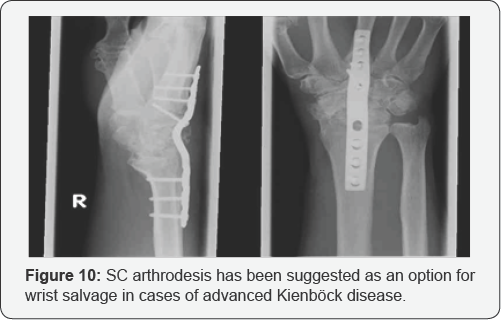

Salvage procedures are reserved for later stages of disease and for failures of other treatments. Proximal row carpectomy (PRC) has been shown to provide relatively good results for Kienbock disease, as well as for other wrist problems [20].Wrist arthrodesis is the final option for patients with global wrist degeneration. Arthrodesis can be achieved successfully following a failed PRC. SC arthrodesis has been suggested as an option for wrist salvage in cases of advanced Kienbock disease [21] (Figure 10). A reasonable approach to determining the surgical treatment of Kienbock disease based on stage is as follows: